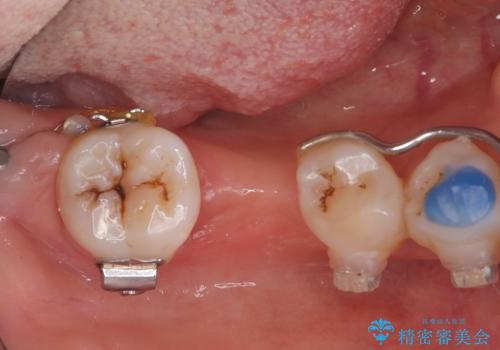

- 歯がぐらぐらしてきて怖いとのことで、当院に来院された患者様です。

右下小臼歯は歯周病で大きな骨欠損を認めていました。

できる限り歯が保存できるように治療したいとのことでエムドゲインを用いた再生治療を行っています。

歯周病の原因に咬合干渉が疑われる為、ワイヤーにて固定を行っています。